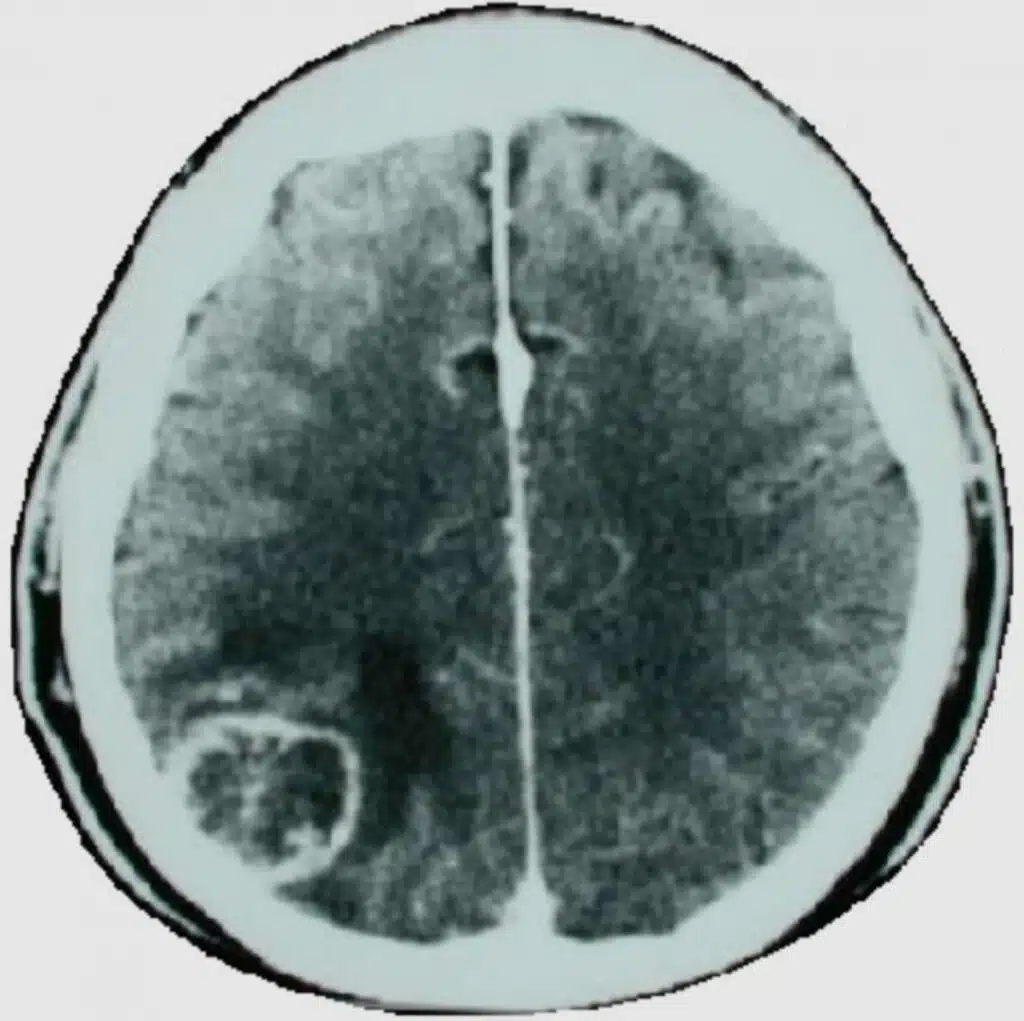

During the second half of the healing phase, harmless brain connective tissue, so-called glia, is stored in the brain. This completely harmless brain connective tissue, which can be stained white with an iodine contrast medium in a CT scan, was previously wrongly considered to be a so-called brain tumor and was operated out with complete ignorance. However, the brain cells themselves cannot multiply at all after birth. Therefore, real brain tumors cannot exist at all.

According to the content of the conflict, a particular area of the brain, already determined in advance, has been “switched,” which can be seen from the 1st second on with our

computed tomogram (CT’s), as a so-called Hamer Focus (HH), and therefore a predictable change in the organ, e.g., cell proliferation or cell reduction or a functional disorder, in the so-called cancer equivalents (cancer-like diseases). Switched over here means that the DHS is “only” the switching process to a particular program so that the organism can cope with the unforeseen situation.

On the brain level, we see that during the healing phase, the HH now gets edema, i.e., it turns dark. The rings in the CT become blurred and dark, and the whole relay in the brain swells enormously.

In the brain, both phases naturally have their HH in the same place but in different states: in the conflict-active phase, always with sharply marked circles, the so-called shooting target configuration; in the conflict-resolved phase, the HH is swollen and edematized.